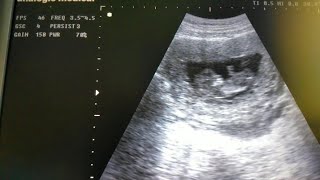

Usg Kehamilan Sendiri 12Mg Gumuss Janinnya Lompat

1.7 K

6:14